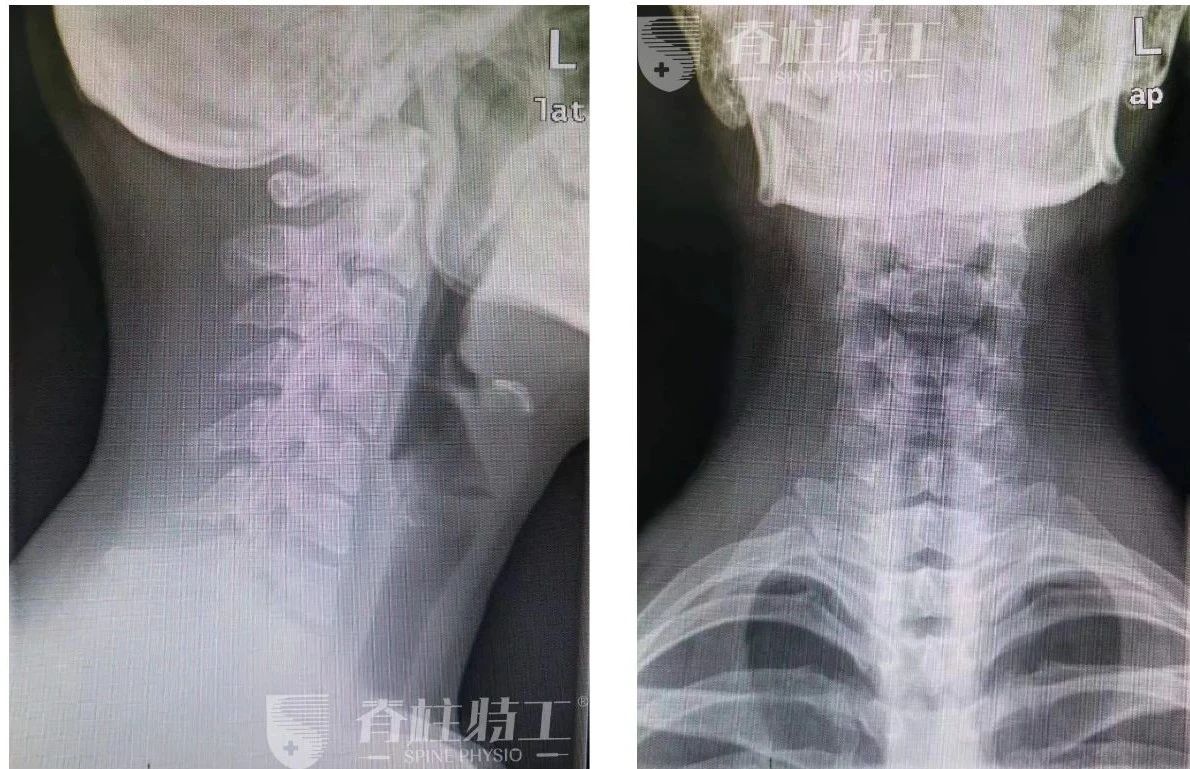

虽然拍片发现 「颈椎曲度变直,有点反弓」 ,但我一直以来都是出现了症状,才开始寻求解决方法,没有做过长期的针对性的治疗。

■ 当时拍的片子